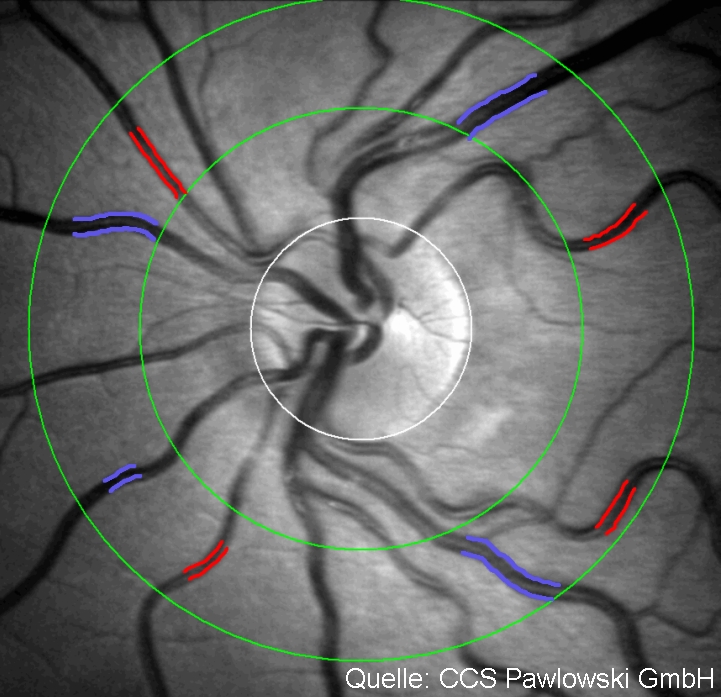

Venenverschlüsse |

Verschluss eines Venenastes

hier Verschluss der Zentralvene

hier im Fluoreszenzangiogramm